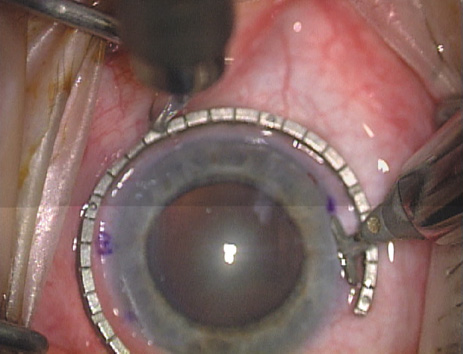

Case 2 is a 79-year-old woman who presented with a very dense left cataract. Her refraction was recorded at −2.25 +2.75 × 125 with a difficult end point. Her manual keratometry and topography measurements were consistent and revealed slightly less than 1.75 D at 120 degrees. Because of the questionable refraction, greater value was placed on the corneal measurements. Based upon the cataract nomogram, the plan was for paired LRIs of 40 degrees to be placed over the steep 120-degree axis (Figs. 1219).

Fig. 12. In this left eye, the steep meridian is at the 120-degree axis and has been delineated by opposing limbal marks. The upper left hand ink mark represents the 6:00 position for orientation. (Reprinted from Hardten DR, Lindstrom RL, Davis EA. Phakic Intraocular Lenses: Principles and Practice. Thorofare, NJ: SLACK Incorporated, 2004, with permission.)

Fig. 13. The incision is begun 20-degrees to one side of the centering mark. (Reprinted from Hardten DR, Lindstrom RL, Davis EA. Phakic Intraocular Lenses: Principles and Practice. Thorofare, NJ: SLACK Incorporated, 2004, with permission.)

Fig. 14. The incision is completed. (Reprinted from Hardten DR, Lindstrom RL, Davis EA. Phakic Intraocular Lenses: Principles and Practice. Thorofare, NJ: SLACK Incorporated, 2004, with permission.)

Fig. 15. Total arc length equals 40 degrees. (Reprinted from Hardten DR, Lindstrom RL, Davis EA. Phakic Intraocular Lenses: Principles and Practice. Thorofare, NJ: SLACK Incorporated, 2004, with permission.)